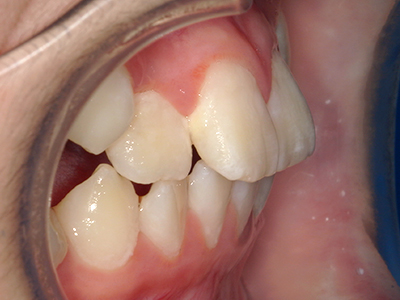

↓ - さまざまな不正咬合が生じる

矯正装置を装着し、調整しながら少しずつ歯を移動させ、歯並びを整えていきます。